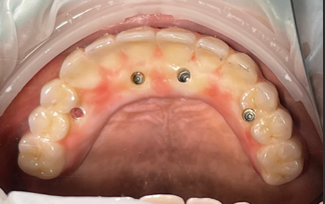

나사로 고정 식이라 넣었다 뺐다 하지 않아요.

더군다나 디지털 가이드를 이용해서

뼈가 얇은 경우에도 정확하게 심을 수 있어요

실제 환자분들의 깨끗한 통지르코니아 잇몸 반응